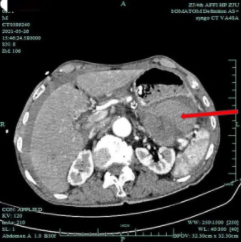

2021年

这次因为腹部剧痛送诊后,专家发现,金大伯的肿瘤已经大了一倍,生长至近 10 公分大小,已经破裂出血。